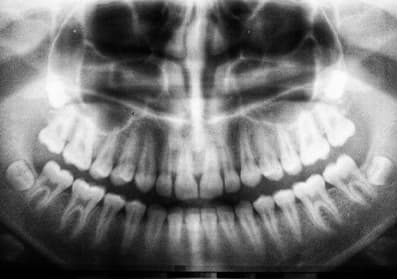

We always aim to restore your teeth to their original form and function.